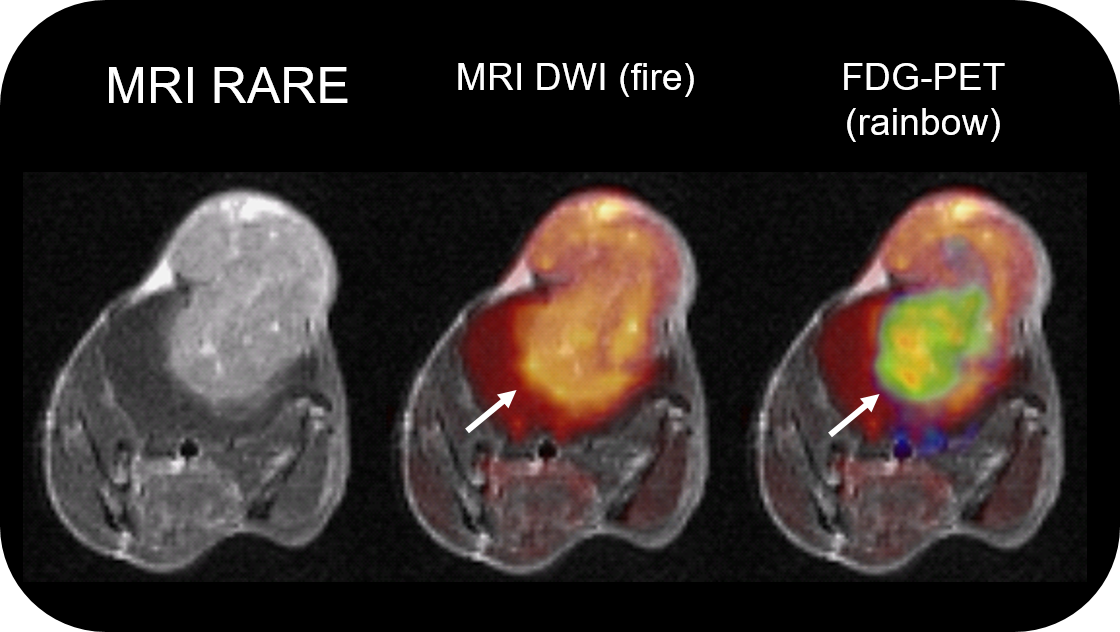

除了PET提供的代谢信息和MR!提供的卓越的软组织对比度,多参数PET/MR成像甚至可以更深入地了解情况,例如在这个小鼠胶质瘤模型研究中,在配备了PETinsert的BioSpec 70/30上进行,其中FDG摄取显示了肿瘤的异质性,对应干低扩散区域,表明细胞高度分裂的位置(白色箭头)。图片来源:比利时鲁汶大学,UHimmelreich.w Gsel.0Casteels, M Riva, and C Deroose。